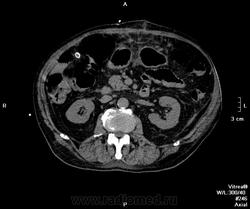

Пациент поступил ко мне через 6 дней после ушивания перфоративной язвы ДПК. УЗИ-сты увидели инфильтративно-жидкостные изменения в зоне оперативного вмешательства, пузырьки газа. Но смутило найденное образование в пространстве между правой долей печени и паранефрием. цель исследования - дифференцировать найденное между инфильтрацией и жидкостным скоплением.

Пациента готовили в течение 2 часов, перорально разведенный урографинчик дробно, и пол станканчика перед исследованием (это важно). Болюс в артериальную и венозную фазы.

мы имеем - задренированное околопеченочное пространство, жидкость в подпеченочном, левом поддиафрагмальном пространстве и по контурам селезенки (серозная), к передне-наружному контуру левой доли печени прилежит ограниченное жидкостное скопление

-ничего криминального между висцеральной поверхностью печени и правой почкой (паранефрий как им угодно) не вижу

-!!! в нативе желудок и петли кишечника не контрастированы - следы контраста в отдельных петлях тонкого к-ка (перед исследованиям он пил, по зонду ничего никуда - ни ни!!!), петли толстого и тонкого кишечника содержат умеренно повышенное количество воздуха и жидкого содержимого, с горизонтальными уровнями

- просвет верхне-горизонтальной ветви дпк в области оперативного вмешательства и зоны сегментарной пластики убудительно не прослеживаеся, представлен зоной инфильтрации, утолщенными стенками кишки, по наружному контуру воспаленных тканей лентовидно расположенные пузырьки воздуха - более вероятно воздух на фоне складок; затеков КВ нет

- воспалительные изменения в проекции лапаротомного доступа, в пжк передней брюшной стенки, в абдоминальной жировой клетчатке и межпетельно

- меня смущает не типичный вид артериальной фазы, и уж тем более венозной

Усиление коркового вещества слабое, задержка начала нефрографической фазы. диаметр почечным артерий около 5 мм, почечных вен -- 10мм. на 60 секунде отсутствует должное конрастирование вен, без признаков патологического сброса

и куда контраст делся из кишечника? (предположим - не развели в кувшинчике, но выпить-то перед исследованием мы ему дали)

ну не глюк ведь??? ни одна вена не усиливается! почему так???